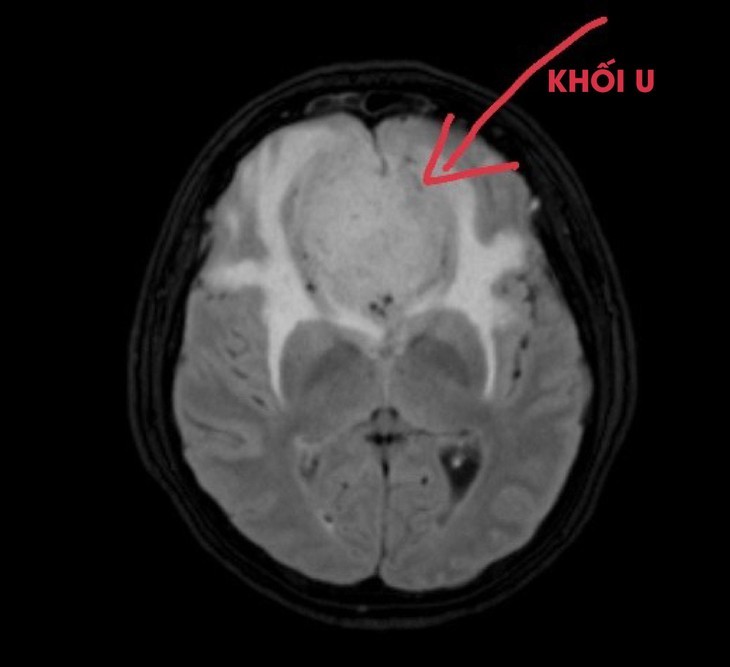

Trong quá trình thăm khám và khai thác tiền sử, biểu hiện bác sĩ đã nghi ngờ bệnh nhân có bất thường về thần kinh nên đã chỉ định bệnh nhân chụp Cộng hưởng từ sọ não. Kết quả chụp của bệnh nhi cho thấy hình ảnh khối u nang vách trong suốt khổng lồ, teo mỏng vỏ não hồi trán trên phải.

Khối u não ở trẻ qua hình phim chụp.

Qua hội chẩn liên viện cùng chuyên gia Bệnh viện Nhi TW, các bác sĩ xác định đây là khối u lớn nên bệnh nhi được chuyển ngay Bệnh viện Nhi TW điều trị.